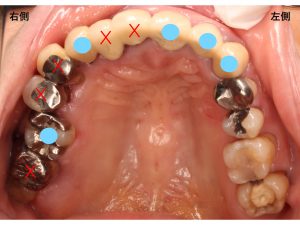

まず初診時の口腔内からみていきます。

上顎です。

上顎の噛み合う面から見た状態です。

上顎の前歯部は、セラミックという素材で作られていました。

以下の赤丸部分です。

上顎では、以下のバツ印が抜歯が必要な状態でした。

バツ印を抜歯し、

青丸部分を土台として

ブリッジを作成することになりました。